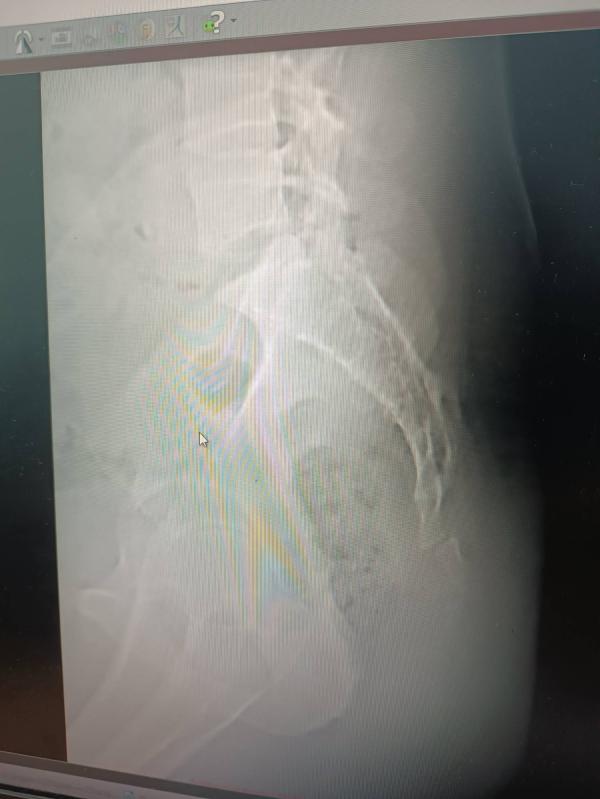

У мужа перелом копчика...